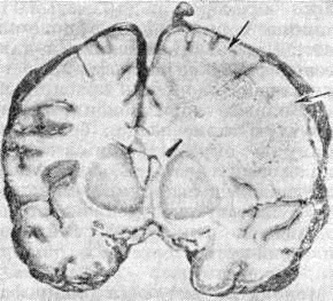

ЛейкоэнцефалитЛейкоэнцефалит (leukoencephalitis; греческий leukos белый + enkephalos головной мозг + itis) — воспалительно-дистрофическое поражение белого вещества головного мозга. Лейкоэнцефалит относятся к демиелинизирующим заболеваниям (смотри полный свод знаний). Впервые заболевание из группы Лейкоэнцефалит описал Дансон (J. Danson) в 1933 год под названием «подострая форма летаргического энцефалита». В 1939 год Петте и Деринг (Н. Pette, G. Doring) сообщили об энцефалите с хронический прогрессирующим течением, несколько отличающимся по клинические, и патоморфологический проявлениям, назвав его узелковым панэнцефалитом. В 1945 год это же заболевание описано Ван-Богартом (L. Van Bogaert) как «подострый склерозирующий лейкоэнцефалит». В дальнейшем Ван-Богарт тщательно изучил клинику и морфологию этой хронический прогрессирующей формы энцефалита. С группой Лейкоэнцефалит также сходны описанный в 1912 год Шильдером (P. F. Schilder) диффузный периаксиальный энцефалит и геморрагический Лейкоэнцефалит, о котором сообщил Херст (Е. W. Hurst)B 1941 год Этиология и патогенез. Предполагается, что Лейкоэнцефалит являются заболеваниями инфекционно-аллергической природы. Дискутируется роль миксовирусов, вирусов кори, бешенства и Herpes zoster как пусковых факторов гиперергического аутоиммунного процесса. Классификация. Выделяют следующие клинико-морфологический формы Лейкоэнцефалит: подострый склерозирующий лейкоэнцефалит Ван-Богарта, периаксиальный лейкоэнцефалит Шильдера, острый геморрагический Лейкоэнцефалит. При Лейкоэнцефалит демиелинизирующий процесс обычно сочетается с поражением нейронов в той или иной степени, поэтому для некоторых его форм употребляется также термин «панэнцефалит». Патологическая анатомия. Макроскопическое исследование мозга при Лейкоэнцефалит выявляет расширение борозд и атрофию извилин. На срезе полушарий определяются различного размера участки деструкции и демиелинизации во всех отделах мозга, преимущественно в белом веществе, но захватывающие различные участки серого вещества коры (рисунок 1). В наиболее поражённых отделах мозг имеет губчатую консистенцию, желудочки мозга умеренно расширены. Гистологический картина характеризуется диффузной подострой воспалительной реакцией с периваскулярной инфильтрацией лимфоцитами и плазмоцитами и очаговой демиелинизацией (рисунок 2). Воспалительные изменения преимущественно локализованы в белом веществе мозга, иногда в коре, подкорковых ганглиях, мозговых оболочках. Разрушается нормально сформированный миелин (миелинокластический тип поражения). Степень демиелинизации и деструкции нервной ткани варьирует в различных очагах. Отдельные мелкие очаги могут сливаться. У краёв очага демиелинизации олигодендроциты увеличены, содержат амфофильные включения, в более поражённых участках они полностью исчезают. Кроме того, встречается много больших причудливой формы астроцитов с гиперхроматическими многодольчатыми или несколькими ядрами. Аксоны остаются относительно сохранными на ранних стадиях процесса, позднее в них могут быть дистрофические изменения. Нейроны коры полушарий большого мозга могут содержать включения двух типов: сферические частицы диаметром 30—40 микрометров и продолговатые, или тубулярные, структуры несколько меньшего диаметра. Включения чаще встречаются при небольшой длительности заболевания. Гистохимический исследования обнаруживают во включениях большое количество белка. В большинстве случаев находят пролиферативную реакцию глии. Глиоз может быть мелкоузелковый или в виде крупных очагов (псевдоопухоль). Диффузное разрастание волокнистой глии приводит иногда к уплотнению мозгового вещества, так что мозг на разрезе имеет хрящевидную консистенцию. Стенки артерий и вен утолщены, с избытком ретикулярных волокон в адвентиции. Клиническая картина. Нервно-психические нарушения являются наиболее ранним проявлением заболевания. Вначале отмечаются жалобы на повышенную утомляемость, вялость, раздражительность, неустойчивость настроения. Постепенно круг нервно-психических расстройств расширяется. Появляется злобность, аффективность, жадность, эгоистичность, жестокость, недисциплинированность, инертность мышления. Больные часто совершают немотивированные поступки, теряют навыки опрятности. |